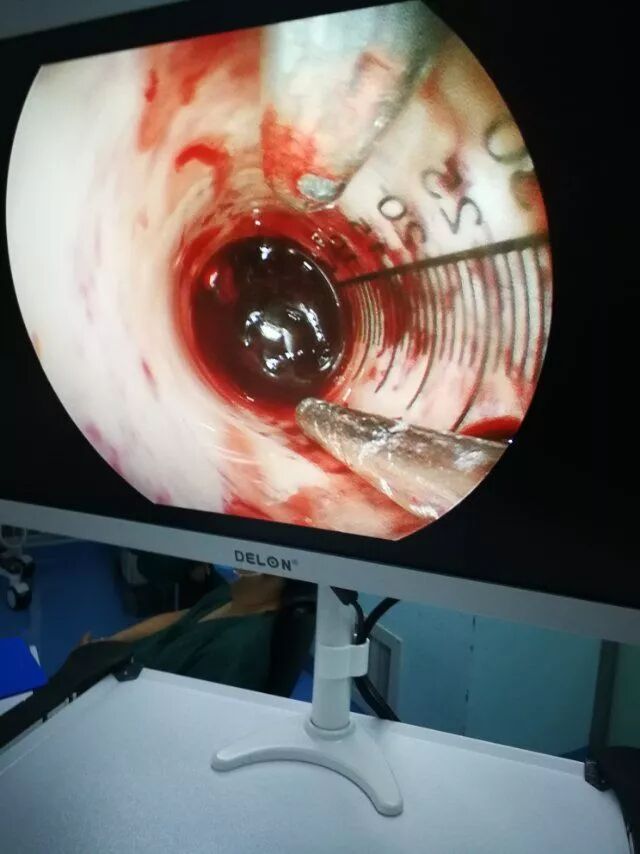

内镜下清血